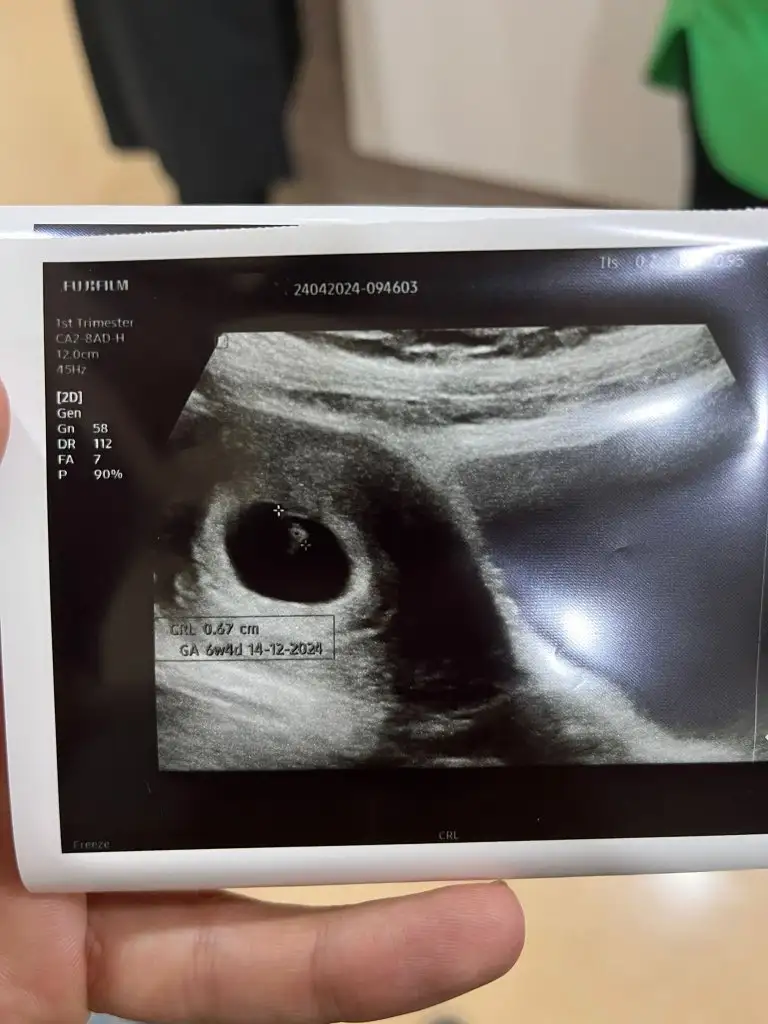

Bu da 6+2 ikendi karından

• 17112804719628535810472540490816.webp

Selisay selam canım banada yorum yaparsan çok sevinirim kardeşimin ultrasonu 6+2 karından ultrason cinsiyeti merak ediyoruz.. sağlıkla gelsin bebişler inşallah

Selisay selam canım banada yorum yaparsan çok sevinirim kardeşimin ultrasonu 6+2 karından ultrason cinsiyeti merak ediyoruz.. sağlıkla gelsin bebişler inşallah Eki Görüntüle 3419352

Merhaba maşallah bu benisimiz de arada kalmış ortada duruyo biraz ama erkek olma olasılığı yüksek görebildiğim kadarıyla kardesinize sevgiler hayırlı dogumlar